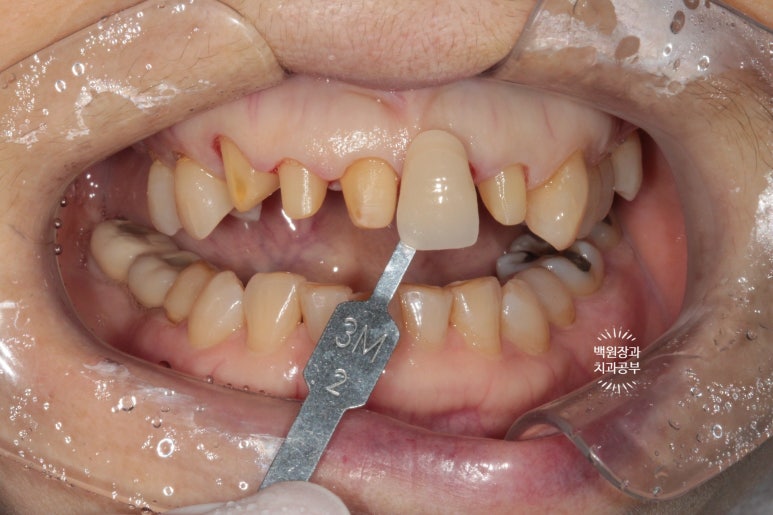

Vita shade guide를 이용하여 색상을 기록한뒤, 준비해두었던 임시치아를 붙여드렸습니다.

앞니 지르코니아 크라운을 셋팅해봅시다.

확실히 가지런해진 모습인데요, 인위적으로 색상이 밝은 것 같다고 다른 치아와 유사한 색상으로 만들어 싶어하셨어요.

음.. 대부분의 환자들이 보통 앞니 크라운 치료시 보다 밝은 색상을 원하시는데, 치과의사가 좋아하는 정확한 내 치아색을 원해하셔서 조금의 수정을 해보기로 하였습니다.